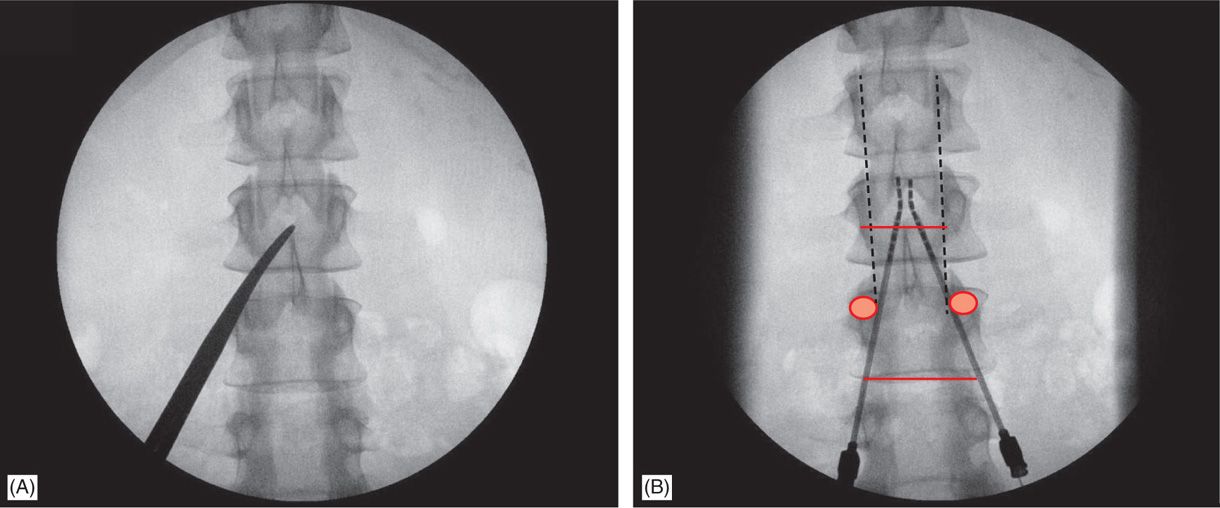

Scs Implantation - Spinal Cord Stimulation: Implantation Techniques / Scs involves percutaneous or surgical implantation of electrodes in the epidural space, with power supplied by an implanted battery.

Scs, lbp, laminotomy, paddle electrodes.